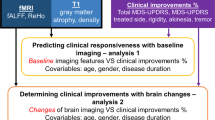

In the current nonrandomized controlled trial, we applied MRgFUS in a sample of TDPD and ET patients with substantial hand tremor to investigate the brain’s functional changes following precise VIM lesioning, particularly the changes in cortical and cerebellar functional connectivity (FC) networks involved in hand movement. We chose the VIM as a target since the current study represents one of the first China-based MRgFUS trials for tremor treatment and as the VIM has the most evidence behind it out of all the targets for both TDPD and ET25,26,27,28,29,30,31. Patients underwent MRI scanning and tremor symptom assessment at baseline (one or two days before the intervention), one day after the intervention, as well as one month, six months, and 12 months later.